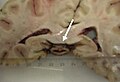

Pineoblastoma

General

• Rare.

• Malignant.

• Males > females.

• Children & young adults.

• Corresponds to WHO IV (ICD-O: 9362/3).

• May be a manifestation of the DICER1 syndrome.[14]